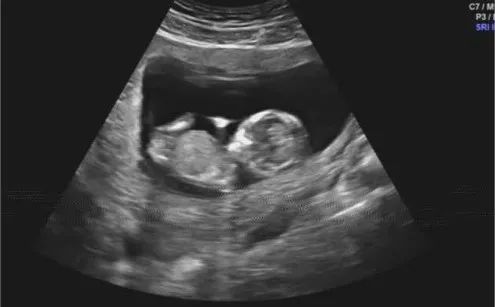

NT是胎儿颈部半透明膜的缩写,是10~13孕周围绕在胎儿颈项后部流动性的半透明蛋白膜。它的厚度与胎儿DS缺陷正相关,并可以通过超声成像测量。

NT排畸检查是指胎儿颈后部皮下组织内液集聚的厚度的检查。通过B超测定颈项透明层厚度,便于及早发现唐氏儿和先天性心脏病的胎儿,并及时予以干预。NT检查是检查胎儿有没有先天愚型,是优生优育必要的检查。

NT的变化与孕周密切相关,所以要求检查的时间范围也就相对固定。11周前难以观察,14周后逐渐消失,因此NT检查佳时间是在孕11周~13周+6天之间进行。